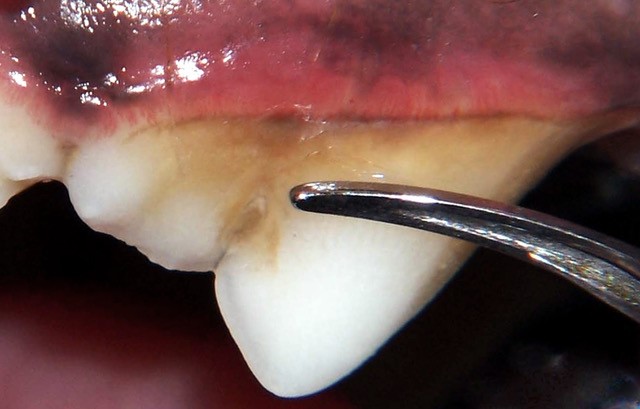

Dental disease begins with a sticky, invisible film called plaque that forms on your pet’s teeth just hours after eating. Plaque is made of food particles, bacteria, and saliva. If it isn’t removed regularly, it hardens into tartar, especially near the gumline. This buildup causes the gums to become red and swollen—a condition called gingivitis—and can eventually damage the bone and tissue that support the teeth. Some pets, especially small dogs and flat-faced breeds like Pugs and Bulldogs, are more prone to developing dental problems quickly due to the unique shape and spacing of their teeth.

Even with excellent home care, pets still need regular professional cleanings done by a veterinarian. These cleanings must be performed under general anesthesia. Anesthesia allows the vet to thoroughly examine your pet’s mouth, clean above and below the gumline, take X-rays, and safely remove any diseased teeth if necessary. Cleanings that don’t use anesthesia may sound appealing, but they only remove surface tartar and can cause pain or injury. Worse, they miss problems hiding under the gums. Dental X-rays are essential because more than half of each tooth is below the gumline, where you can’t see damage with the naked eye. Issues such as root infections, broken roots, and bone loss can only be detected with X-rays.

Sometimes pets need more than just a cleaning. They might have a fractured tooth, crowded teeth that rub the gums, or other painful dental issues. Broken teeth can expose the inner pulp and cause serious infections. These teeth may need to be removed or treated with a root canal. Some pets have misaligned teeth that can cause injuries inside the mouth. In such cases, a veterinary dentist can address the issue using braces, selective extractions, or other specialized procedures. Veterinary dentists are specially trained to handle complex dental issues using specialized tools, including X-rays, surgical instruments, and advanced techniques.